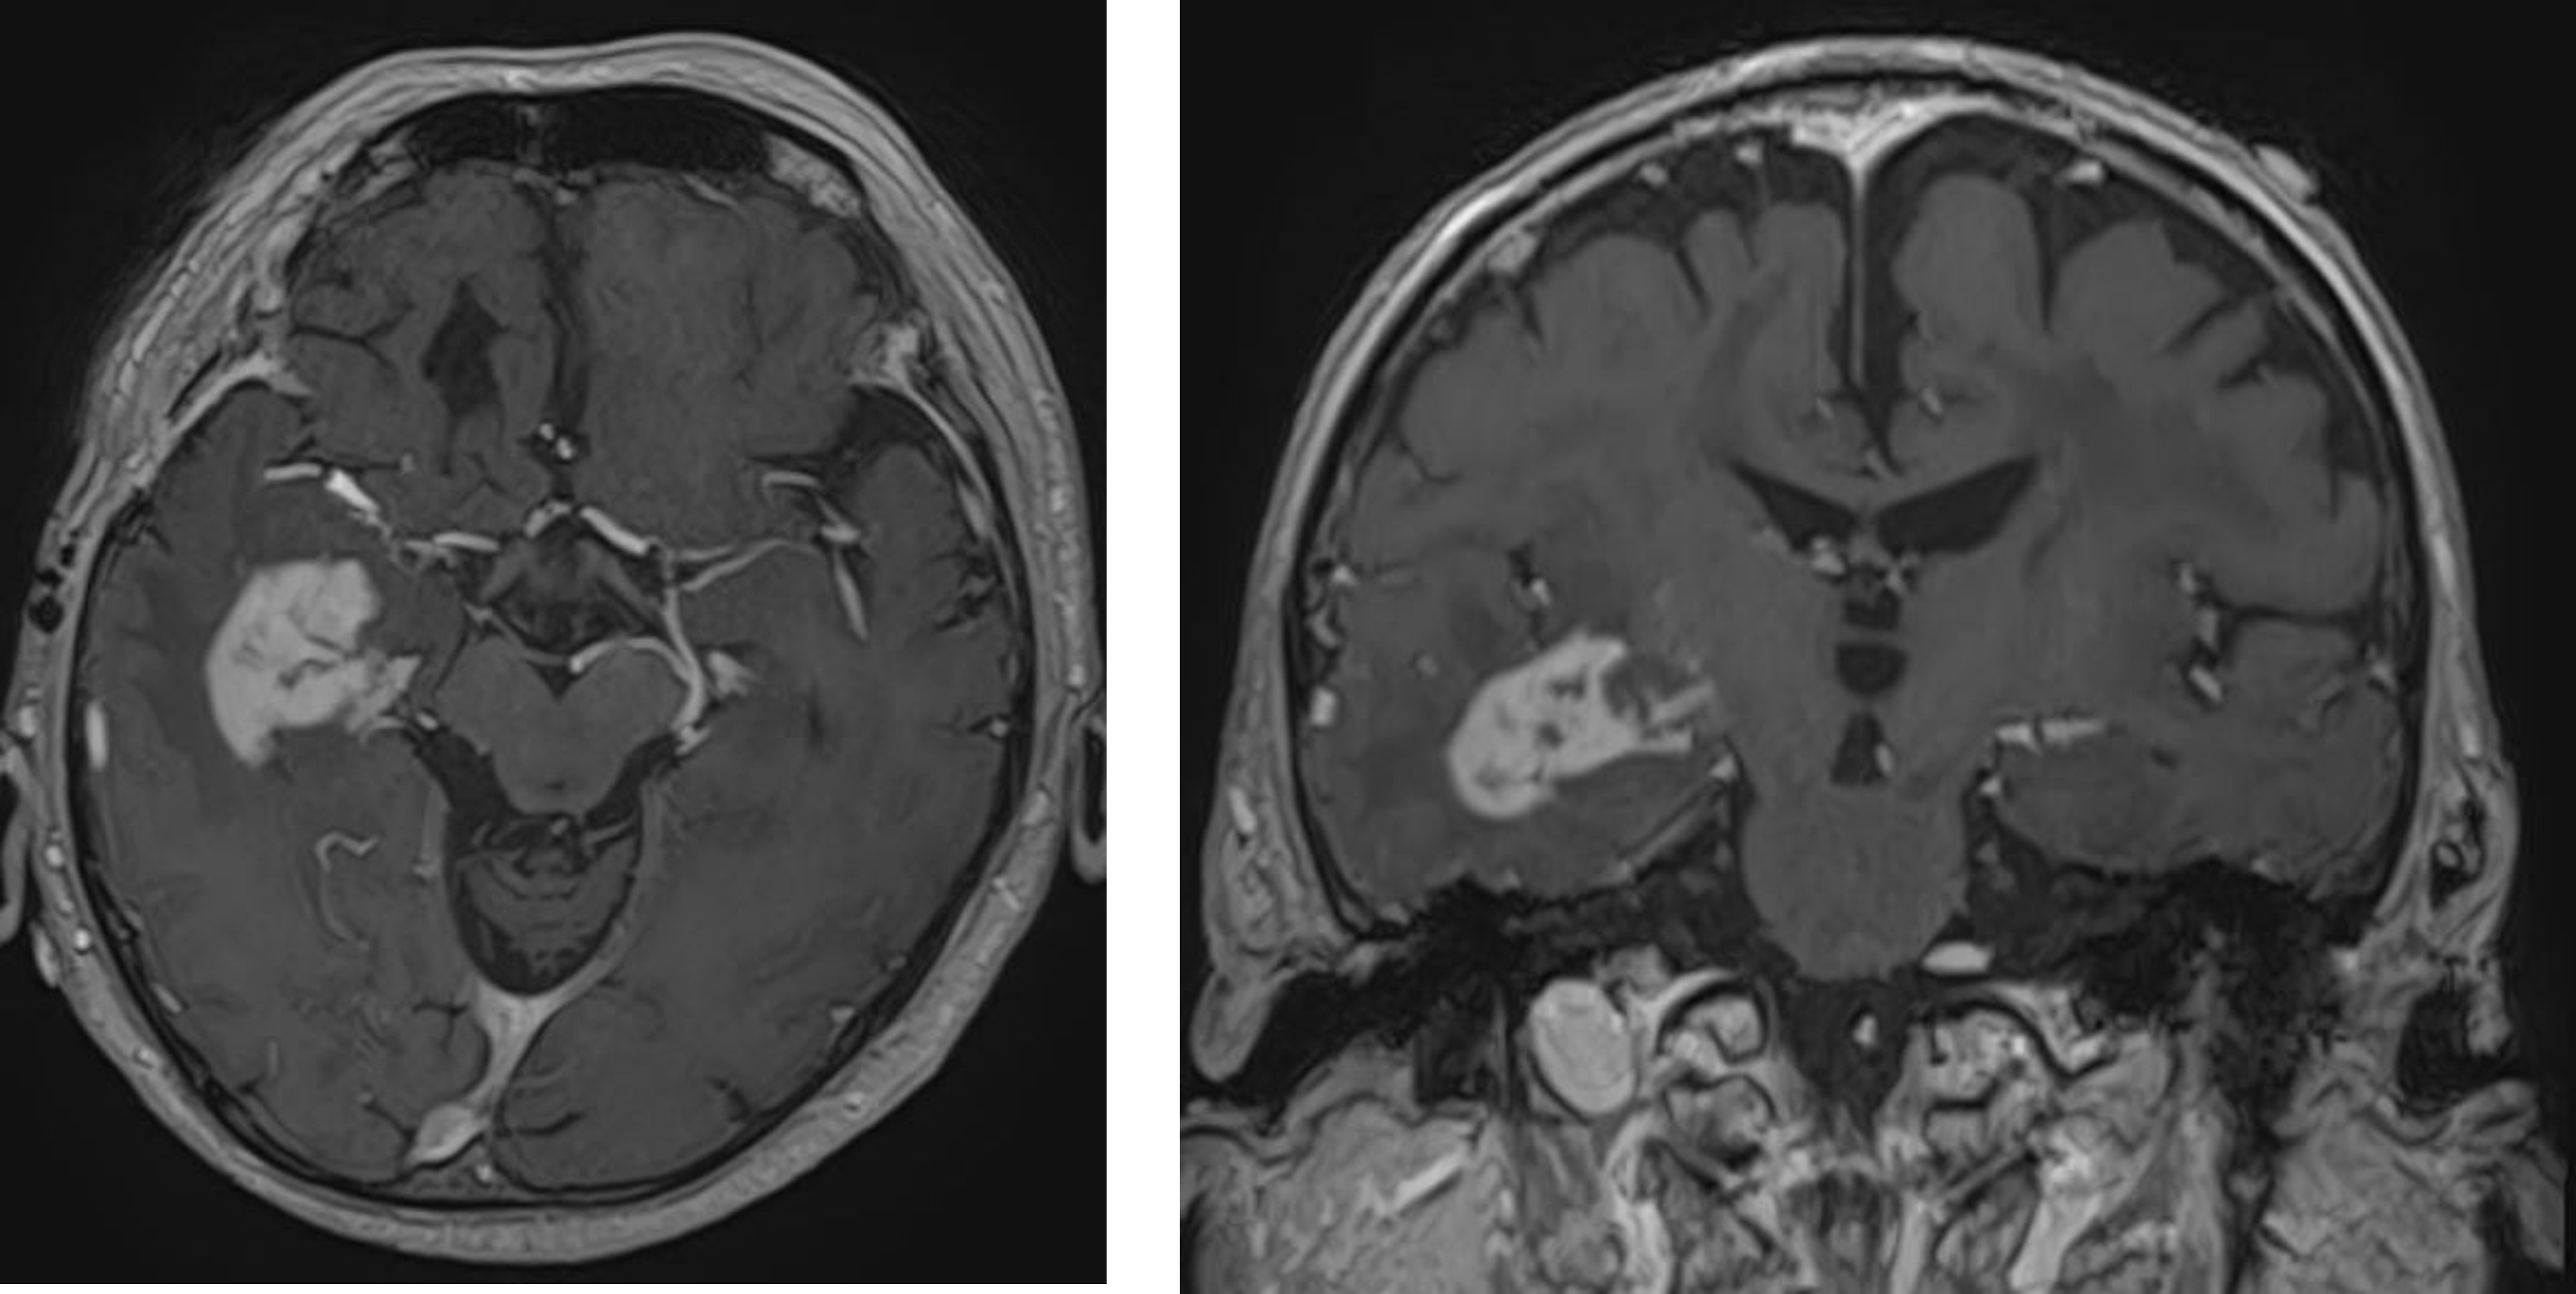

髄膜腫

髄膜腫は原発性脳腫瘍のうち最も頻度の高いものです。緩徐な増大を来し無症状であることも多く、脳ドック検査などで偶然発見される場合もあります。治療後も再発や転移を起こさない良性の経過を来すものが多いですが、一部に細胞分裂が速かったり、何度も再発を来すような悪性度の高いものが存在しますので注意が必要です。小さく進行がゆっくりであるものは経過観察を行うことが一般的です。摘出の難易度を左右する要因は、腫瘍の部位、大きさ、硬さ、栄養血管の豊富さなどがあげられます。腫瘍が大きい場合は、周囲の脳や神経、正常血管と癒着している場合があります。頭蓋内の深部に存在するものは手術の難易度が高い場合があります。手術は血流が多い症例もあり、術前に血管内治療で栄養血管を塞栓した方が手術時の出血量を減らせたりすることが多く、この方法を取り入れています。